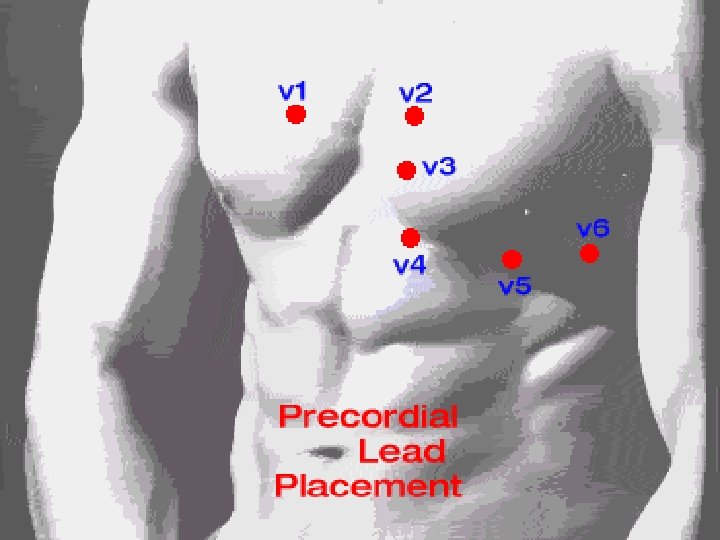

Conduction • Occurs approximately every 0. 8 seconds. • Electrical impulse can be recorded on an EKG • Used to detect abnormal activity or disease.